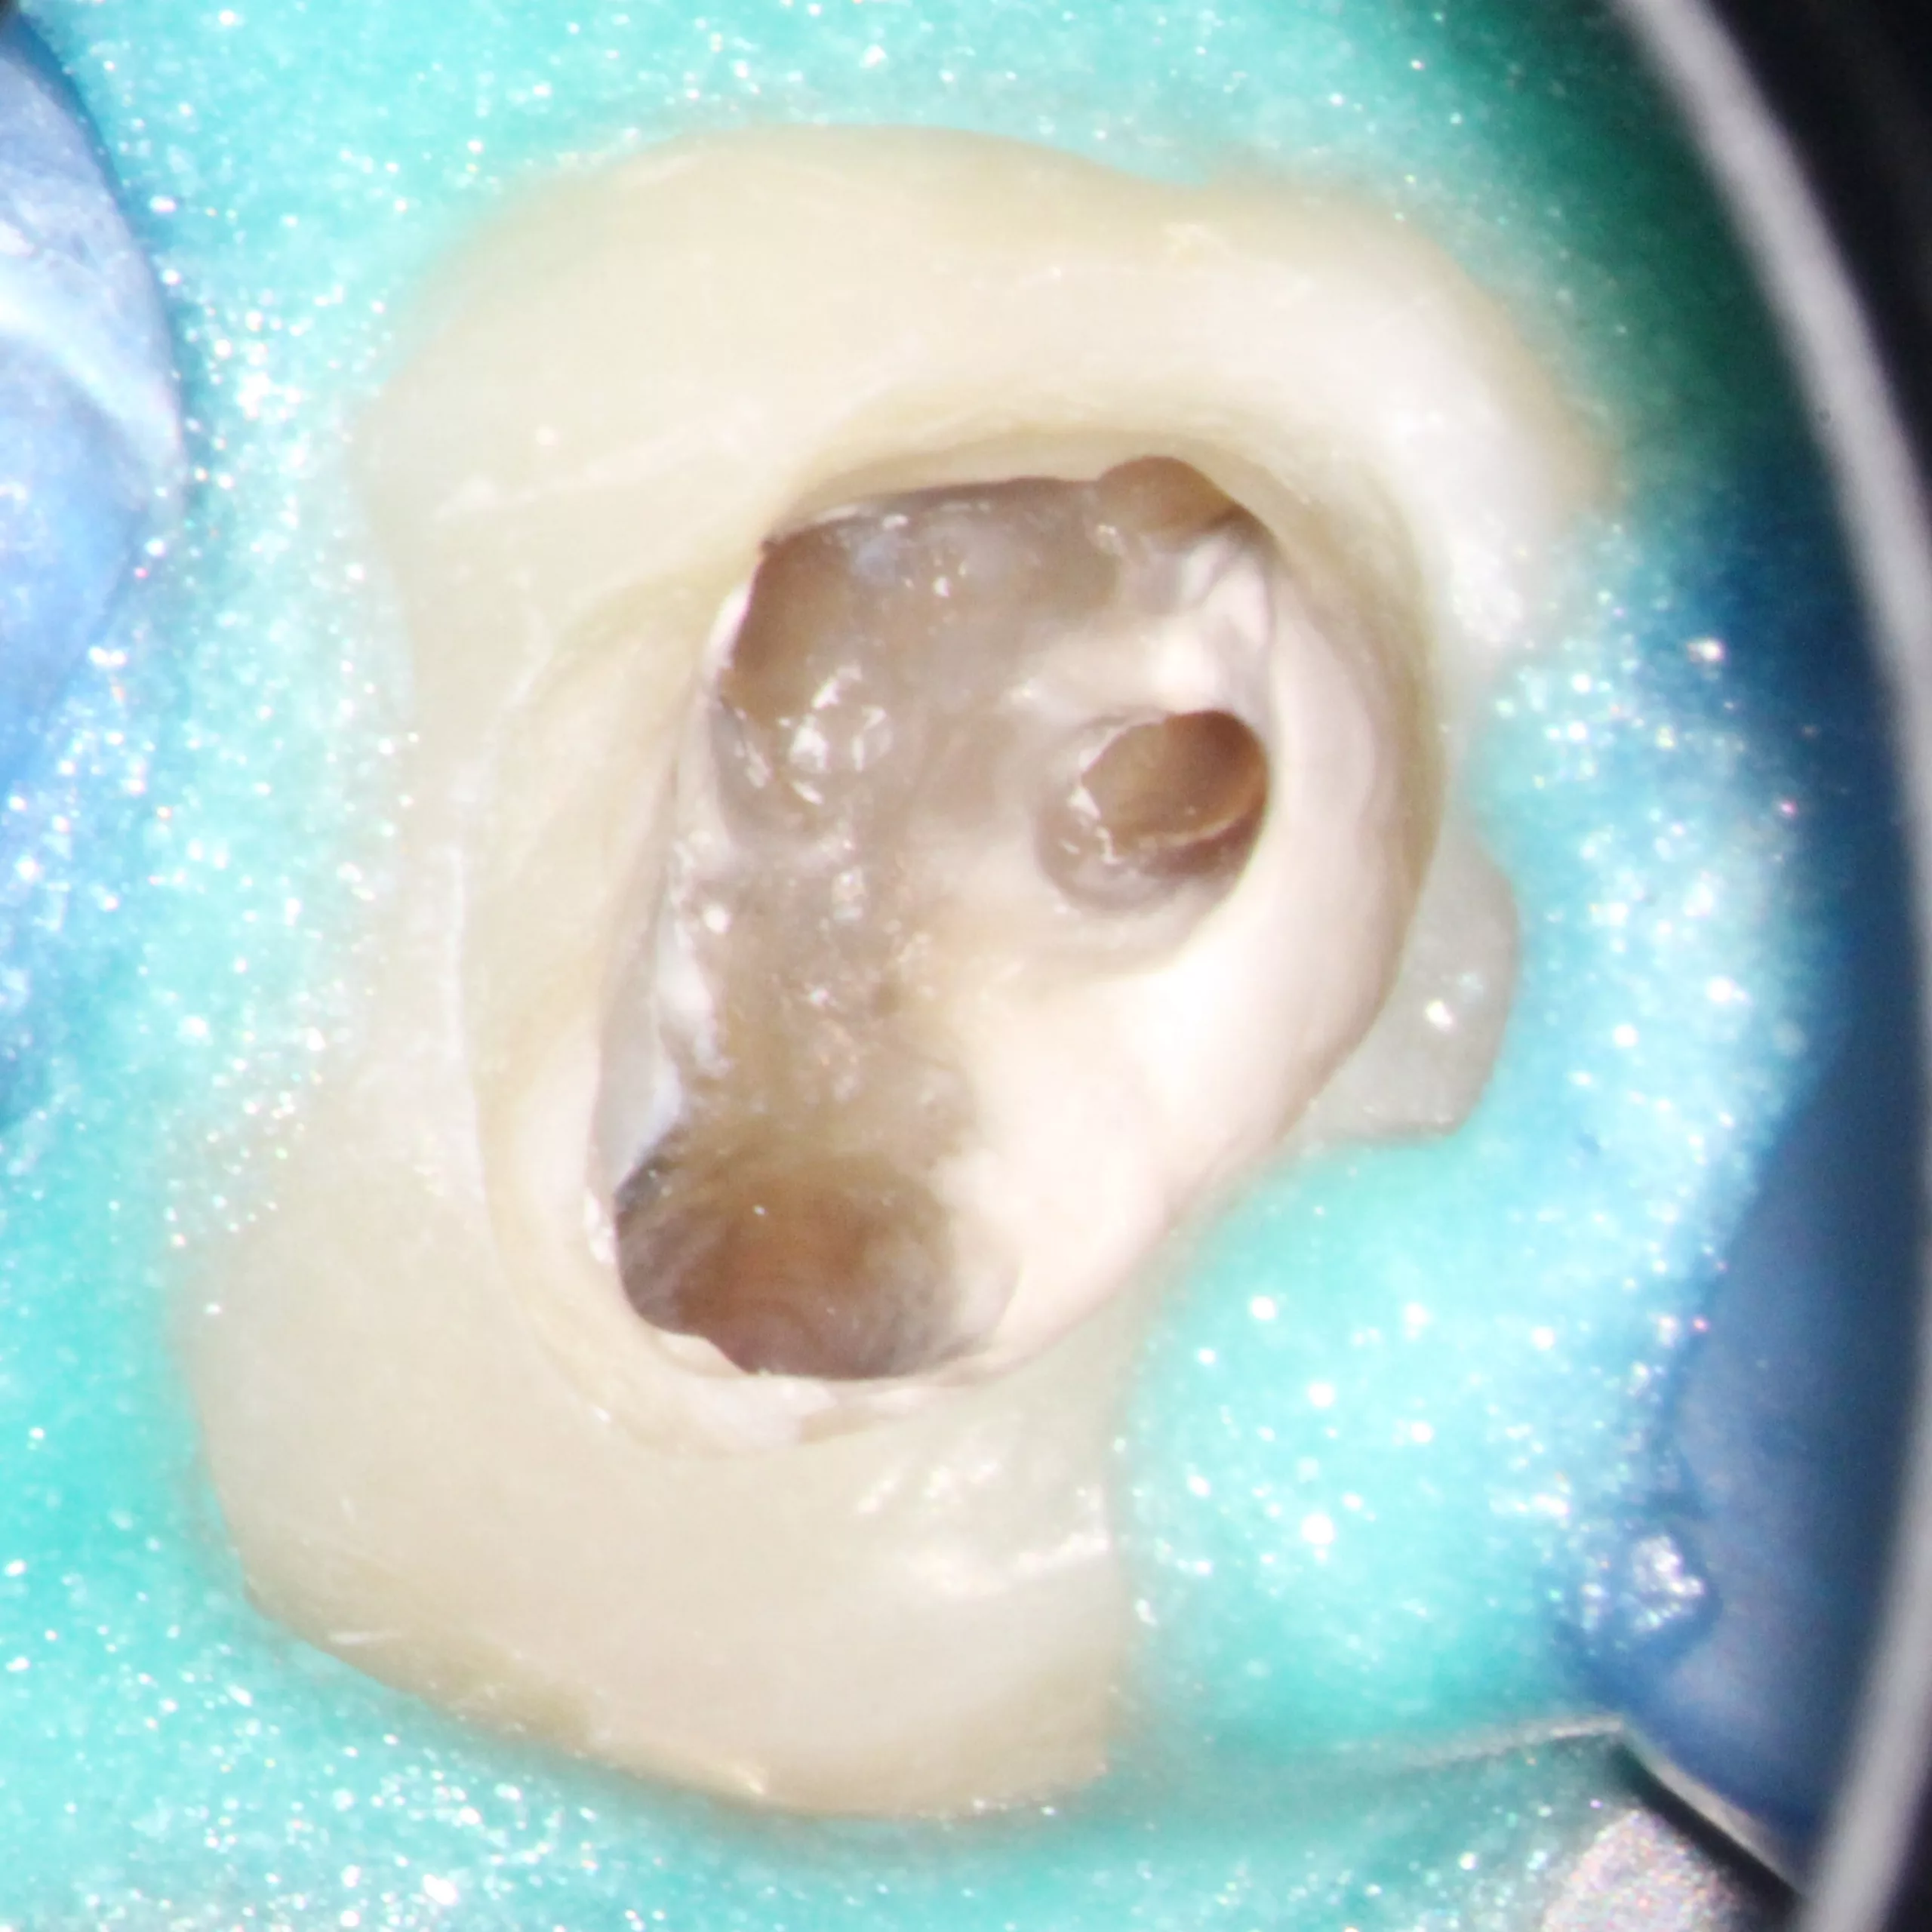

Die Abbildung 54 zeigt das Kanalsystem unmittelbar vor der Wurzelkanalfüllung, die Abbildung 55 nach der vertikalen Kondensation des Wurzelfüllmaterials. Um eine weitere Schwächung des Wurzeldentins zu vermeiden, favorisieren wir eine passive Stiftinsertion ohne weitere Stiftbettpräparation. Auch bzw. insbesondere, wenn ein Zahn mit einem Stift-Stumpf-Aufbau versehen werden soll, sollte ein zusätzlicher Hartgewebsverlust möglichst vermieden werden, der die Prognose des Zahnes zusätzlich verschlechtern würde [17,33,88,93]. Die Schlussfolgerung aus den angeführten Studien ist, auf eine Stiftbohrung zu verzichten, wenn ein Wurzelkanal im koronalen Drittel weit und gerade genug ist, um einen Stift aufnehmen zu können. Dies gilt insbesondere für Seitenzähne, die eher einer axialen Belastung ausgesetzt sind, und ist nur möglich, wenn der Stift unmittelbar nach der Wurzelkanalfüllung eingebracht wird.

Die Abbildung 56 zeigt die Einprobe eines Glasfaserstiftes (EasyPost, Dentsply Sirona). Nach Vorbehandlung des Stiftes mit dem Visalys Restorative Primer und nach Reinigung des Kanalsystems mit AH Cleanser (Dentsply Sirona) sowie der Applikation des Visalys Tooth Primers im Zahn erfolgte die zeitgleiche Verklebung des Glasfaserstiftes mit Visalys CemCore (diesmal in der opaken Variante) und dem internen Aufbau des gesamten Zahnes. Die Abbildungen 57 bis 59 zeigen das 2-schichtige Einbringen von Visalys CemCore Opaque nach einer Zwischenhärtung des 1. Inkrements für 40 Sek., die Abbildung 60 die Röntgenkontrolle der Wurzelfüllung und des Stumpfaufbaus. Der okklusale Anteil der Kavität wurde wenige Minuten später von einem Kollegen okklusal reduziert und mit einem klassischen lichthärtenden Komposit definitiv versorgt.